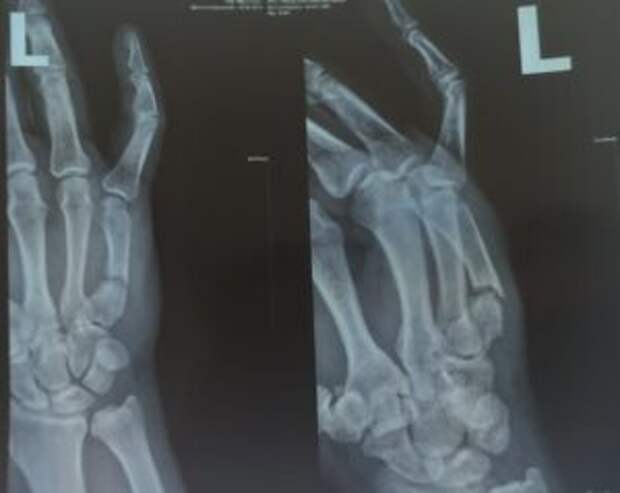

Diagnóstico: Fractura por arma de fuego del quinto metacarpiano con desplazamiento. Se ha formado una articulación falsa, se requiere fusión ósea.